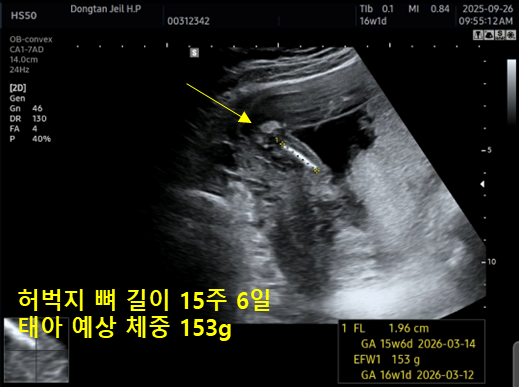

| 허벅지 FL | 1.96 cm | 15주 6일 | 허벅지뼈 길이 |

| 추정 체중 EFW | 153 g | 16주 1일 | 태아 예상 체중 |

전체적으로 주수와 거의 비슷하게 성장하고 있어서 크게 벗어난 부분이 없다고 하셨어요.

머리는 16주 2일, 배는 16주 6일로 조금 더 크게 나왔고, 허벅지는 15주 6일 정도로 살짝 작게 찍혔는데, 의사 선생님께서 “범위 안에 다 정상”이라고 말씀해 주셔서 안심했답니다.